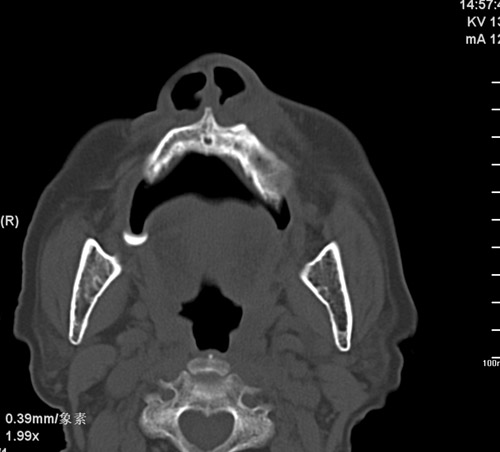

标题: CT17755:女,74 左鼻旁肿胀半年,临床以左上颌窦旁占位行CT [打印本页]

标题: CT17755:女,74 左鼻旁肿胀半年,临床以左上颌窦旁占位行CT

ct考虑鼻前庭囊肿 或鼻翼基底部慢性炎症,左上颌窦少许炎症 请指教

1)考虑左侧鼻前庭囊肿并感染。2)双侧上颌窦炎。

左侧鼻前庭囊肿并感染。双侧上颌窦炎。支持